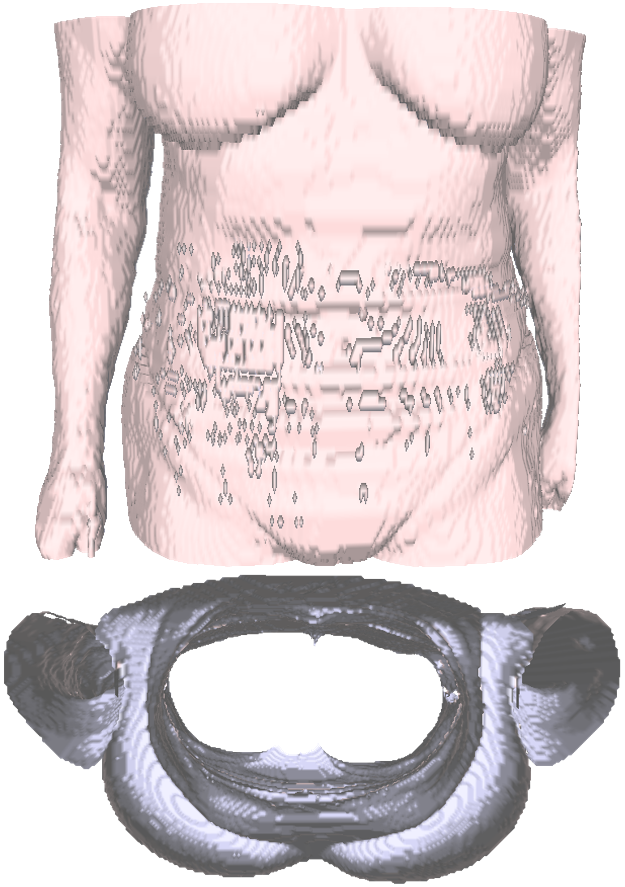

The novel co-registration is divided into two main software components integrated into the image fusion system. The first aims to segment the external skin surface of patients acquired by MR/CT, while the second seeks to co-register the segmented skin surface with the 3D surface obtained by the camera.

Skin segmentation

The segmentation of the 3D surface representing the patient’s skin is used to bridge the seamless integration of the heterogeneous data sources involved in the system. Indeed, extracting the body surface from volumetric imaging facilitates subsequent analyses and enables the processing of lighter data. The segmentation of the external body surface is computed according to the Hounsfield value (CT) or intensity level (MR), set as a default parameter, and is represented as triangle mesh. Given a CT/MR image paired with the skin iso-value, the proposed segmentation identifies the subject’s skin surface, which is used as input for the co-registration. The general idea is to leverage the differences in intensities between the air and the body surface. The segmentation proceeds one slice at a time, starting from a background pixel. Then, the growth of the background region proceeds iteratively based on the pixels’ adjacency and stops when it encounters a pixel whose grey value is higher or equal to the iso-value of the skin. Through this region-growing algorithm, the evaluation expands only where the air is present; the body will be segmented as a whole object by exclusion.

Fig. 2 describes the segmentation method developed. We create a mock-up grid of the same dimensions of each slice, and each element of the grid is related to the pixel in the original slice that presents the same location (Fig. 2(a)). Initially, all the grid elements of the mock-up are associated with the same initial value equal to 2. On the image slice, the starting pixel must belong to the background, e.g., the pixels in the corners, since the subject’s body is typically located in the centre of the image. Once the starting pixel has been selected, we check if it belongs to the background through its intensity level in the original slice. A pixel is considered background if its intensity remains under the skin isovalue in the image. In contrast, if its intensity is above the isovalue, it indicates that we encountered the body edge. If the pixel belongs to the background, the corresponding element in the mock-up grid is associated with 0, and the pixel is marked as visited. Then, we select its neighbouring pixels, which initialise the list of pixels to be subsequentially visited (Fig. 2(b)). Iteratively, we check if the first pixel of the list belongs to the background. If it belongs in the background, we proceed as before and update the list by removing the just visited pixel, marking it as visited and adding its neighbourhood. Pixels that have already been visited before must not be inserted in the list again (Fig. 2(c)). If the pixel in the original image is above the skin isovalue, then we assign the value of 1 to the corresponding element in the mock-up grid. Moreover, we do not insert the pixel’s neighbourhood in the list (Fig. 2(d)). At the end of the process, the mock-up grid presents a value of 0 in the background, a value of 2 inside the subject’s body (i.e. the initial value of all the elements in the mock-up grid) and 1 in correspondence with the skin. The same procedure is applied to all the slices in the volume. Then, the segmented volume undergoes the marching cube algorithm [LC87] to extract a 3D surface mesh of the segmented skin, representing the input for the co-registration phase to match the MRI and the 3D surface acquired by the camera. To improve the segmentation, we add padding around each slice coloured with the minimum value appearing in the image to guarantee that it will be considered background. In this way, the algorithm proceeds through the padding pixels toward the slice’s end. The padding is helpful in case the MR/CT bed has been acquired with the patient. To reduce the overall computational time for skin segmentation, we can sub-sample each slice and each set in the case of high-resolution MR/CT images. The intensity value for the skin, i.e. the iso-value needed as an input parameter to the segmentation algorithm, is easily retrievable according to the specification of the MR/CT acquisition machine. Indeed, usually, each manufacturer has standard values for each imaging modality.

Skin co-registration

To align the MR/CT image with the US probe, the 3D surface acquired by the camera, which is in the same reference system as the US probe and of the magnetic tracking, is rigidly co-registered with the patient skin segmented from the MR/CT images. The output of the co-registration is a translation vector and a rotation matrix, which co-register the segmented surface to the 3D surface acquired by the camera (i.e., the Intel RealSense in the experimental setup), minimising the corresponding misalignment. The co-registration takes the segmented surface extracted from the anatomical images (MRI/CT), the 3D surface acquired by the camera and a reference virtual landmark as inputs. The 3D surface must be acquired by the 3D camera with a frontal view, following the guidance provided by the camera to minimise acquisition errors. The segmented surface is oriented consistently (i.e., head-feet, right-left) to avoid errors related to body symmetries. The operator manually selects one corresponding landmark point on each input surface to align the two surfaces through an intuitive interface. Thus, the landmark is exclusively virtual and does not require any external physical placement. A pipeline composed by orientation adjustment through Principal Component Analysis (PCA), surface sub-region selection and tuning (region of interest), and various coregistration refinements leveraging the Iterative Closest Point algorithm (ICP) allows for accurate alignment of the segmented surface with the surface acquired by the camera (Fig. 3). Then, the computed roto-translation is applied to the volumetric data to put the MR/CT images in the same reference system of the US probe, thus enabling the fusion of the MR/CT image with the US image since the tracking system tracks both the 3D camera and the US probe. This result will allow the radiologist/surgeon to navigate the MR and US images simultaneously during the US examination or preoperatively. To optimise the time to rigidly register the segmented surface with the 3D surface acquired by the camera, the segmented surface is cut to get only the front part of the body. This way, the relevant part of the segmented surface undergoes the registration. To cut the surface, we consider the angle between the normal at each surface vertex and the sagittal axis: the vertices associated with an angle smaller than 90°are selected as part of the front surface.

The segmentation (i.e., the voxel labelling) and mesh extraction have a computational cost linear to the number of voxels composing the volumetric image. Table 1 reports the timing of each algorithm step on an 11th generation Intel(R) Core(TM) i7-11700k 8 core. To better integrate the approach with existing clinical workflow, we tested its robustness to subsampling. Indeed, given the computational cost property of the method, even a light subsampling could drastically improve the performance in terms of time required for the segmentation to complete. Fig. 5 shows how skin segmentation remains clean and accurate given an image and its subsampled version. We subsampled a volume image by a factor of two in each direction. The only difference is in the resolution of the surface, which is a direct consequence of the lower resolution of the subsampled original image. To confirm the maintained accuracy of the segmentation at different image resolutions, we computed the distance distribution between the surfaces extracted from a volume image and its subsampled version. In this case, the higher distances correspond to those slices and pixels missing in the subsampled version of the image, and the value of the distance is coherent with the changed dimension of the voxels. The 3D skin segmentation, contrary to AI methods, does not require any training and consequently does not require a large data set or various acquisition of diverse imaging modalities, contributing to the method’s generality. The skin segmentation has been designed to be as general as possible regarding the anatomical area scanned (e.g., head, breast, total body and abdomen) and the acquisition modality (e.g., MR, CT, PET). We tested the quality of the segmentation on different anatomical volume images, such as CTs and MRIs (Fig. 6), obtaining satisfactory results.